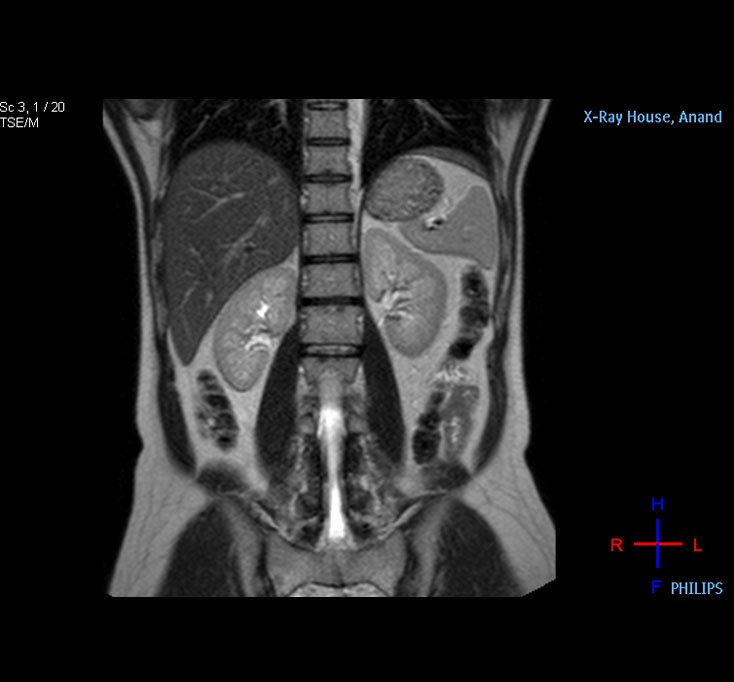

Kidney MRI